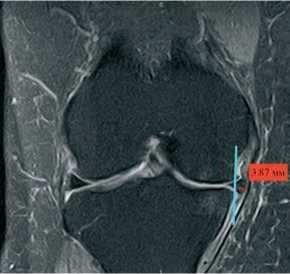

МРТ коленного сустава выполняли до операции и через 12 мес. после операции, оценивая экструзию прооперированного мениска в T2-режиме во фронтальной проекции от медиального края большеберцовой кости, не считая остеофит, до мениска в области его наибольшей его экструзии. (рис. 1) Данные исследования были выполнены на аппаратах мощностью не менее 1,5 Тесла. Экструзия мениска оценивалась одним специалистом по описанной выше методике.

Рисунок 1. МРТ коленного сустава пациента А. фронтальная проекция Т2 режим. Метод оценки уровня экструзии

Средняя величина экструзии мениска до операции составила (4,06±0,82) мм, после операции (2,67±0,71) мм (р > 0,05) (табл. 2), что явилось статистически значимым, т.е. экструзия мениска сохранилась, хотя ее степень все же несколько уменьшилась (используемый метод: парный t–критерий Стьюдента). При этом у пяти пациенток (15,6 %) отмечено уменьшение только на (0,38±0,1) мм, то есть осталась практически на прежнем уровне. При проведении анализа влияния степени экструзии мениска на функциональный результат по KOOS до и после операции, установлены статистически значимые изменения (рис. 8) (р < 0,001) (используемый метод: парный t-критерий Стьюдента).